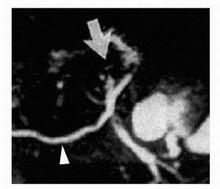

圖5:ERCP顯示短的腹側胰管,符合胰腺分裂,輕微的腺泡顯影。